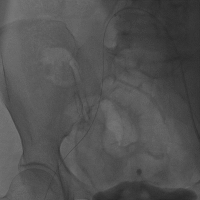

手术过程

刘先宝教授代替王建安院长分享了手术过程,首先,应进行心电图检测、动脉穿刺、临时起搏器植入、导尿管等准备工作。开始手术后,第一步应在对侧进行股动脉穿刺,然后植入保护导丝,选用JR 3.5X4.0,在造影图的情况下在手术侧进行精准穿刺,保证穿刺在血管正中央,尽可能减少血管并发症的发生。并进行血管闭合器预埋,左右岔开20°左右。随后置入大鞘,注意动作轻柔。(Figure 8)

Figure 8

1. 右侧股动脉穿刺

2. 置入大鞘

最后再次测量跨瓣压差(Figure 12),提示压差较术前显著改善,然后进行主动脉根部造影,提示瓣膜位置理想和形态良好,无明显瓣膜漏。并进行股动脉造影,观察有误血管并发症。(Figure 13)

Figure 12

术后测压

Figure 13

9. 造影结果

10. 股动脉造影